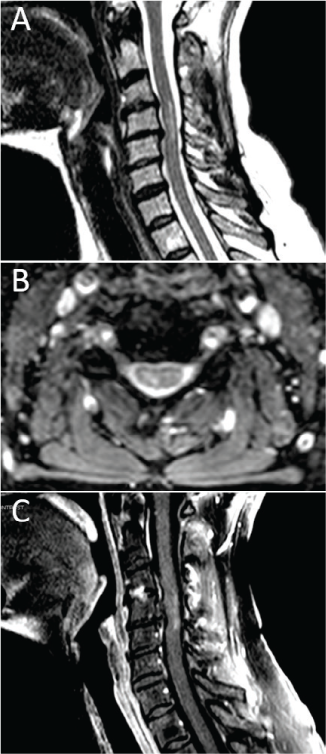

A 65-year-old white woman with a history of TM presented with long-standing central neuropathic pain. She was initially evaluated at an outside hospital in October 2013 for right hand paresthesia with accompanying neck pain followed by lower extremity weakness, right arm incoordination and weakness, urinary retention, torso band-like tightness, and impaired ambulation. Progression to nadir developed over approximately 24 hours. Neuroaxial imaging showed a C3-5 lesion on T2-weighted sagittal and axial sequences, with mild ill-defined peripheral enhancement on postgadolinium T1-weighted sequences (Figure 1). Mild foraminal stenosis was noted, although flexion/extension radiographs indicated preserved cerebrospinal fluid signal surrounding the cord. No flow voids were noted. Given the magnetic resonance imaging findings in the setting of symptoms attributable to the described lesion, the presence of a sensory level, progression to nadir between 4 hours and 21 days, the presence of oligoclonal bands, and a thorough autoimmune evaluation to rule out other causes, the diagnosis of TM was made in concordance with the 2002 TM diagnostic criteria.8 Muscle and nerve conduction studies were performed, and the results were unremarkable. The patient underwent 5 days of high-dose corticosteroid therapy and had modest improvement in her neurologic status.

Magnetic resonance imaging showing a C3-5 lesion after presentation of symptoms